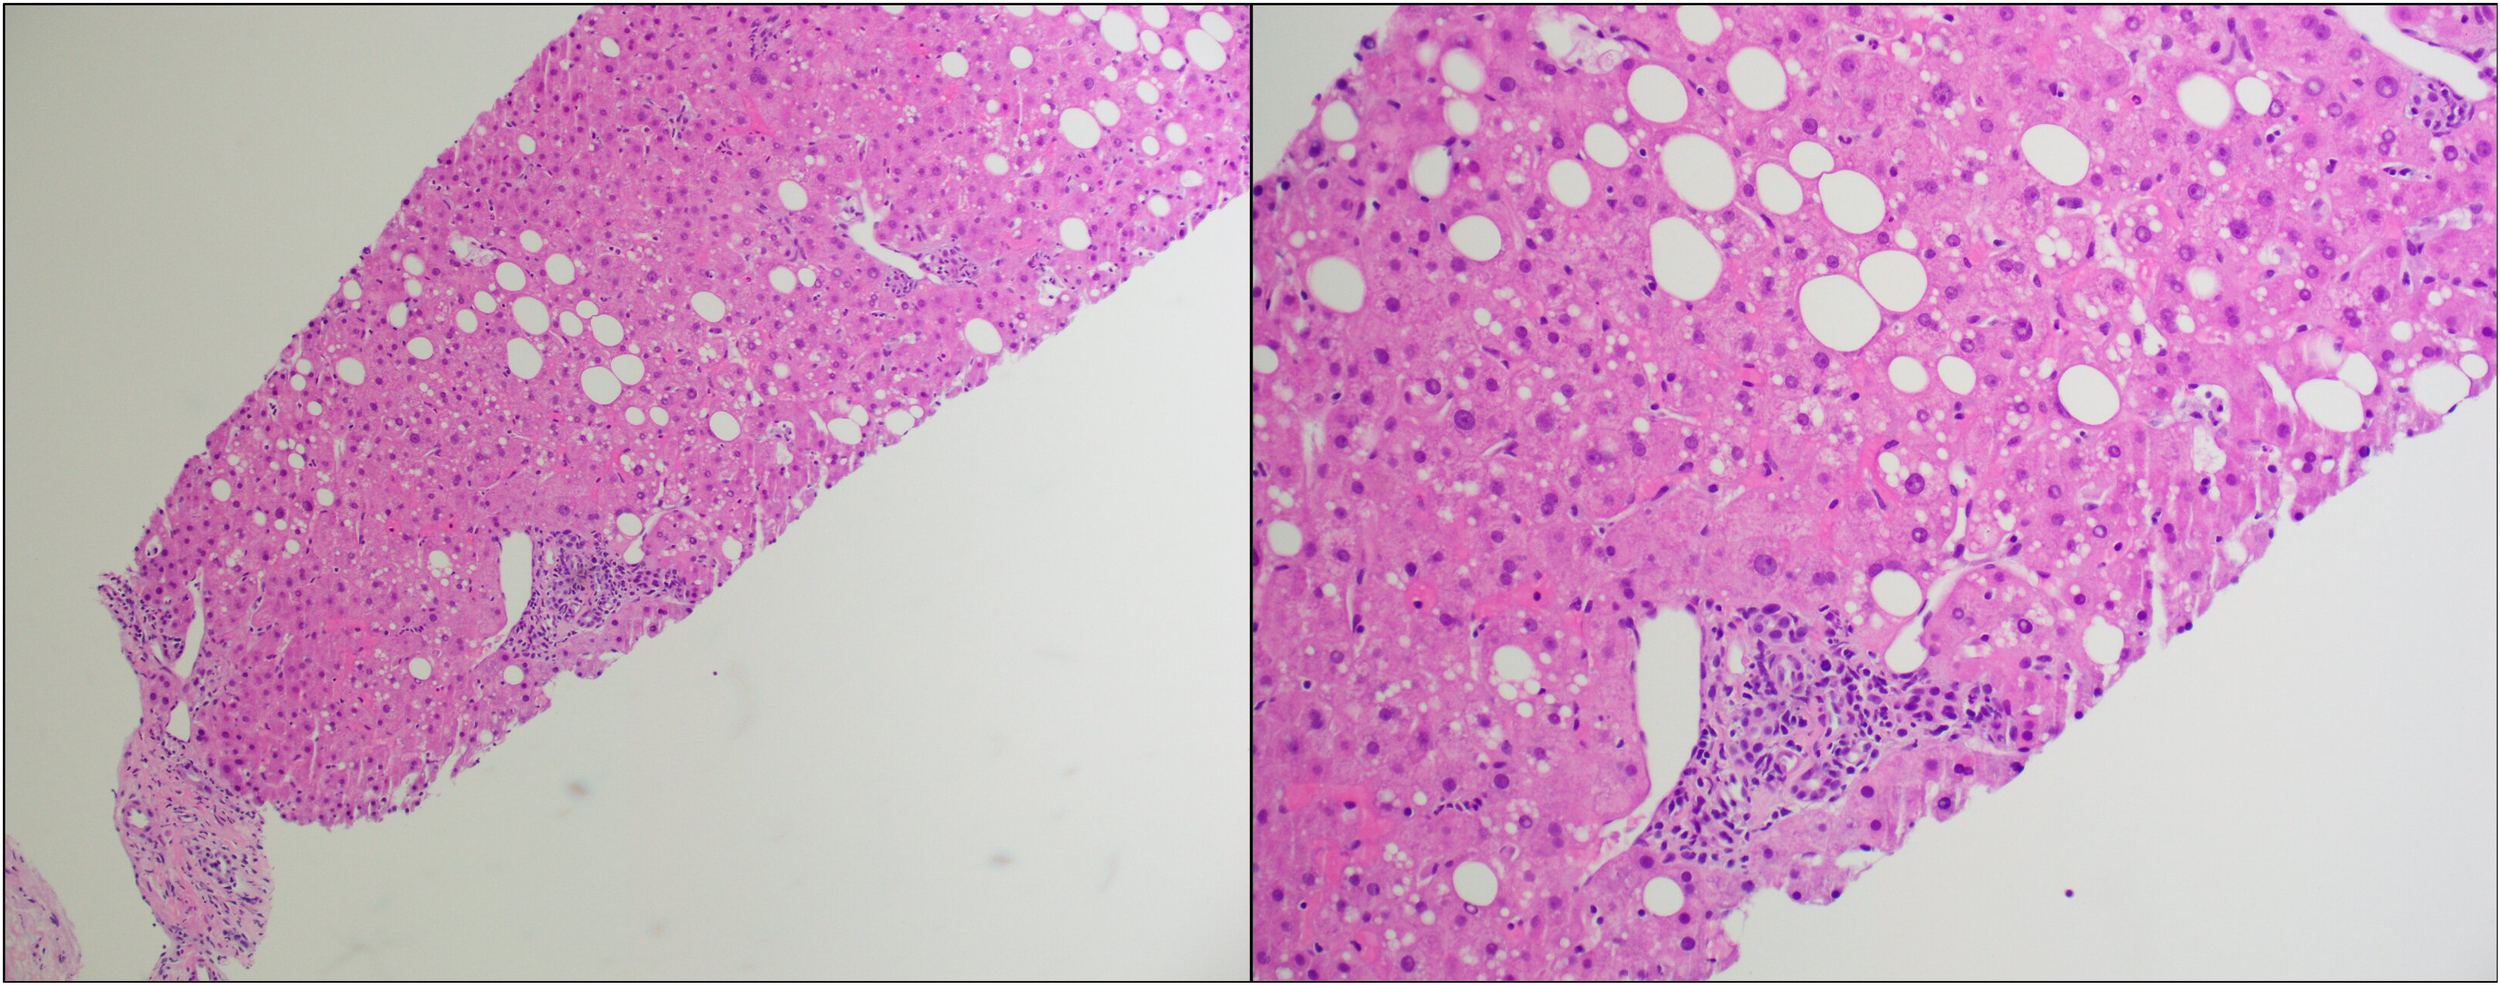

On day +209, the patient was admitted to USC Norris Cancer Hospital due to the suspicion of steroid-refractory liver cGVHD given continuously increasing levels of T.Bili and transaminases (T.Bili, 2.9 mg/dL; ALP, 287 U/L; ALT, 682 U/L; AST, 595 U/L) concurrent with outpatient steroid treatment. The patient further underwent liver biopsy after admission. The histopathological examination of the biopsy sample revealed features most compatible with GVHD (Figure 1). Predominantly lymphocytic inflammation was observed in the portal tracts along with a few neutrophils and eosinophils. A majority of the bile ducts showed inflammatory infiltration and/or damage. In addition to these, the lobules showed mild macrovesicular steatosis and prominent sinusoidal Kupffer cells.

Figure 1

Hematoxylin and eosin (H&E) stain of the first liver biopsy at low power (left) and high power (right).